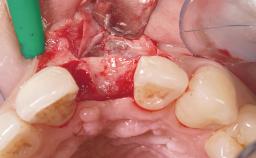

Immediate Flapless Placement of an Implant in a Maxillary Left Central Incisor Site

A 42-year-old female patient was referred to our clinic at the School of Dentistry of the University of São Paulo in November 2004, presenting a deficient restoration in the upper left central incisor. The clinical examination revealed no gingival retraction or any signs of gingival inflammation and, therefore, previous periodontal treatment was not considered. The patient presented a high lip line at full smile and a thin tissue biotype. This combination characterized a high-risk situation from an anatomic point of view, which required careful preoperative planning and cautious surgical execution.

Placement Protocol Immediate implant placement

Loading Protocol Immediate

Provisional Implant-Supported Prosthesis Prosthodontic margin < 3 mm apical to mucosal margin Prosthodontic margin < 3 mm apical to mucosal margin